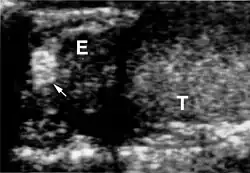

Das klinische Spektrum der Erkrankung umfasst neben den Affektionen von Augen und Kleinhirn das Auftreten von Hämangioblastomen im Bereich des Hirnstamms und des Rückenmarkes. Sodann werden Nierenzellkarzinome (Erkrankungsrisiko liegt bei 25 – 45 %, meist ab dem 50. Lebensjahr), Pankreaszysten, Phäochromozytome, Nebenhodenzysten und eine Polyzythämie beobachtet.

Die Diagnose VHL-Syndrom wird beim Vorhandensein von kapillären Hämangioblastomen (gefäßreichen Tumoren) im ZNS oder der Netzhaut des Auges gestellt. Weitere zum VHL-Komplex gehörende Tumoren (Phäochromozytom, Nierenzellkarzinom) oder eine entsprechende Familienanamnese treten hinzu. In der Kernspintomografie stellen sich die Hämangioblastome als kontrastmittelaufnehmende Knötchen dar.